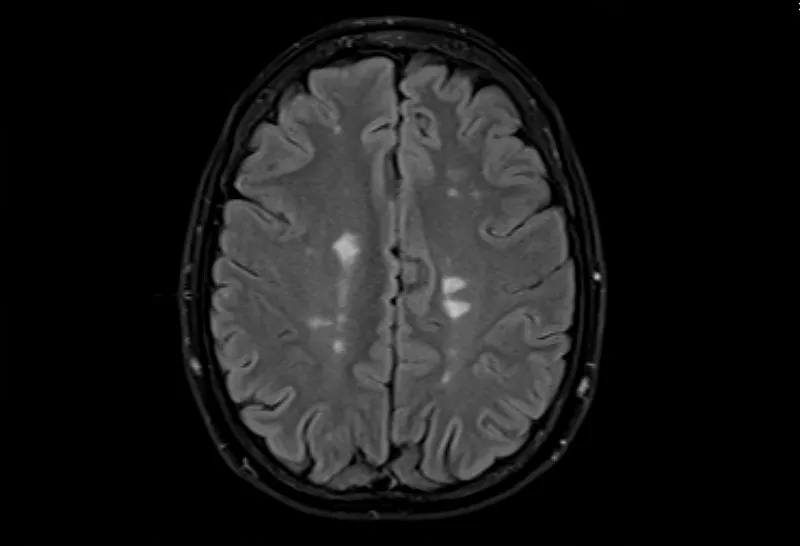

• 大腦的MRI掃描可以顯示損傷區域,但沒有單一的測試可以診斷MS。

多發性腦硬化癥的磁共振成像,軸位Flair視圖

測試的組合用于診斷MS。最好的測試是對您的大腦和脊髓進行核磁共振檢查,以檢測損傷區域。您可能還需要進行血液檢查、腰椎穿刺和測量神經活動的測試。